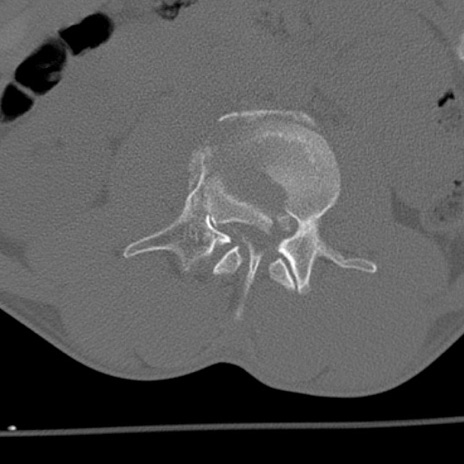

症例3 腰椎CT(横断像)

腰椎CT